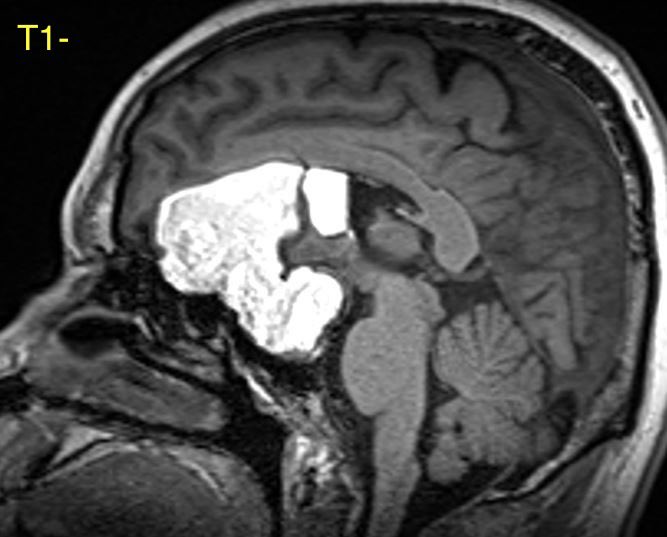

What is the most likely diagnosis in this 30 y/o patient with history of seizures presenting with severe headache?

More images in ๐Ÿงต

Additional images ๐Ÿ‘‡